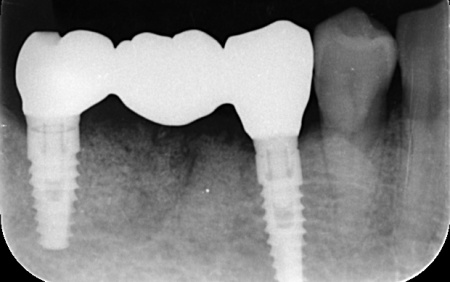

詳しく調べるためにレントゲン撮影を行った結果、どちらの歯も歯根が割れていることが確認できました。

それぞれのメリットとデメリットをお伝えしたところ、患者様は「できるだけ違和感がなく噛めるようになりたい。またなるべく短期間で治療を終えたい」と希望されたため、抜歯と同時にインプラントを埋め込む抜歯即時埋入法を提案し、同意いただきました。

まず、右下奥歯(第2小臼歯、第1大臼歯)を抜きます。

周囲の骨や歯茎への影響をできるだけ抑えるよう配慮しながら処置を行い、抜歯した部位にインプラントを埋め込みました。

抜歯後にできた穴とインプラントの間には隙間が生じるため、骨の再生を助ける目的で骨補填材を使用しながら、丁寧に縫合しました。

3ヶ月後、インプラントと骨がしっかりと結合したことが確認できたため、被せ物を作製するための型取りを行います。

被せ物には、人工ダイヤモンドと呼ばれるほど高い強度をもつ、ジルコニアセラミックを使用したブリッジを製作しました。